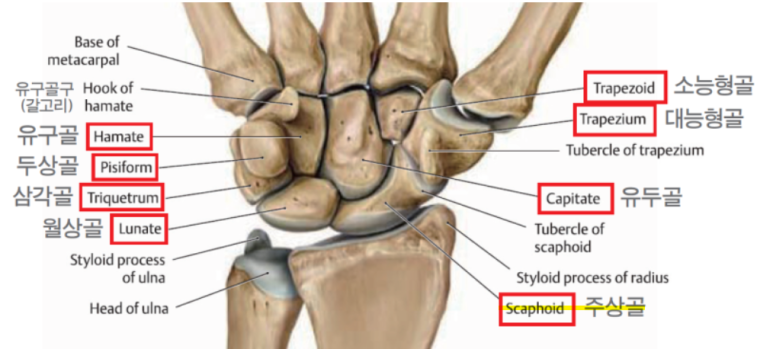

2. 해부학

- 손목에 작은 뼈들은 8개로 구성되어있습니다.

- 근위열 4개뼈

- 주상골(scaphoid), 월상골(Lunate), 삼각골(Triquetrum), 두상골(Pisiform)

- 원위열 4개뼈

- 대능형골(Trapezium), 소능형골(Trapezoid), 유두골(Capitate), 유구골(Hamate)

- 근위열 4개뼈